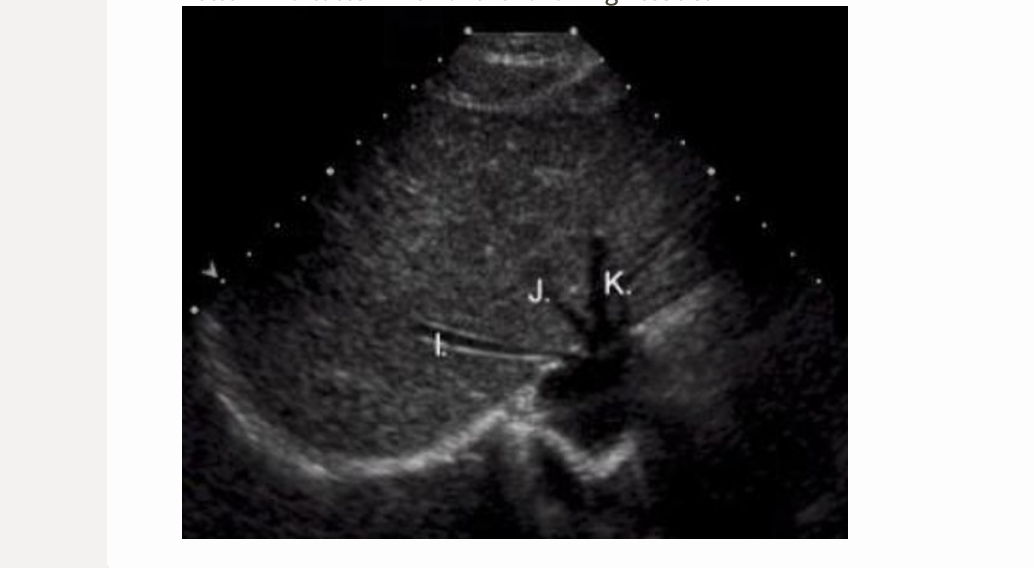

![<p>[IVC = posterior to caudate lobe]</p>](https://knowt-user-attachments.s3.amazonaws.com/37ddafef-a01e-4241-a6eb-4fd43401e918.png)

[IVC = posterior to caudate lobe]

IVC = posterior to caudate lobe